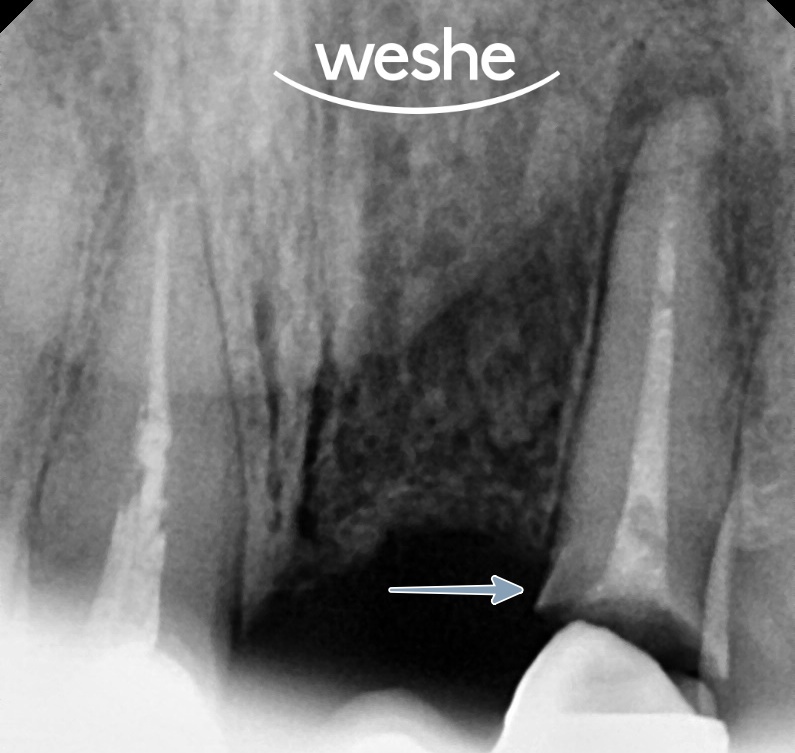

방사선 사진상 지대치에서

특히 22번에서

심한 2차 우식(재발 충치)이 관찰됩니다.

보철물 아래 치아 구조가

충치로 인해 상당 부분 손상된 상태로

이것이 보철물 탈락의 직접적 원인입니다.

20250604

일반적으로 이런 경우

치아 구조가 잇몸 위로 충분히 남아있지 않아

발치를 고려하게 됩니다.

하지만 방사선 사진을 자세히 분석하면

치근 길이가 양호하게 유지되어 있습니다.

치근이 건강하고 길이가 충분하다면

이를 보존할 가능성이 존재합니다.

문제는 충치로 인해 손상된 부위가

잇몸 아래 깊은 곳까지 진행되어

보철 제작을 위한 공간 확보가

어렵다는 점입니다.